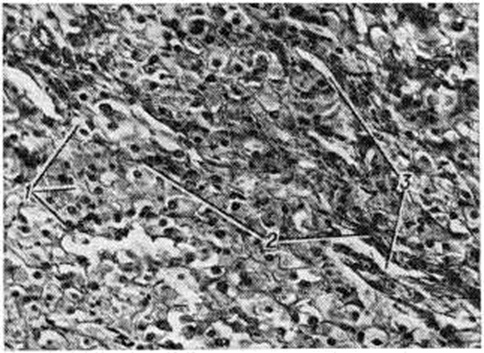

Микроскопическое строение опухоли характеризуется значительным разнообразием, которое зависит прежде всего от величины, формы и функционального состояния опухолевых клеток, а также от состояния стромы опухоли. Вместе с тем для Текома характерны два основных типа клеточных элементов: эпителиоидные и веретенообразные. Разнообразие Текома объясняется, в основном, соотношением клеток этих типов и наличием большого количества переходных форм между ними. Гистологически различают также два основных типа Текома, опухоли одного из них образованы эпителиоидными клетками, сходными с клетками внутренней теки (оболочки) фолликулов (theca interna folliculi), опухоли другого типа образованы веретенообразными клетками, придающими им сходство с фибромой яичника. От фибром такие Текома отличаются прежде всего своей способностью синтезировать половые стероидные гормоны (смотри полный свод знаний), кроме того, клетки паренхимы Текома в подавляющем большинстве случаев содержат в цитоплазме липидные включения, преимущественно свободного или этерифицированного холестерина (смотри полный свод знаний), и каждая клетка паренхимы Текома, в отличие от клеток фибром, окружена аргирофильными волокнами (смотри полный свод знаний). Опухоли этого типа образованы переплетающимися пучками веретенообразных клеток без чётких клеточных границ с относительно большими, вытянутыми, интенсивно окрашивающимися ядрами, иногда могут быть видны нежная хроматиновая сеть и чётко различимые ядрышки. Строма опухоли представлена рыхлой соединительной тканью, иногда отмечают фиброз и гиалиноз стромы. Капиллярная сеть таких Текома хорошо развита, но при обычном микроскопическом исследовании она не бросается в глаза. Опухоли второго типа часто содержат то или иное количество эпителиоидных клеток, располагающихся, в основном, по периферии в виде гнезд или тяжей.

Эпителиоидный компонент в обоих типах Текома представлен большими округло-полигональными клетками, формирующими тяжи, поля и гнезда, разделенные соединительнотканными прослойками с большим количеством капилляров (рисунок).

Клеточные границы хорошо различимы, цитоплазма обильная, оксифильная, мелкозернистая с разным количеством различных по размеру вакуолей. Вакуолизация цитоплазмы этих клеток обусловлена растворением липидных включений в процессе гистологической обработки ткани. Ядра эпителиоидных клеток большей частью округлые, относительно большие, часто с чётко различимыми ядрышками. Локализация ядер и их структура нередко зависят от количества липидов в цитоплазме: чем больше число липидсодержащих включений в цитоплазме, тем ближе к периферии клетки располагается ядро и тем меньше оно по размеру и плотнее по консистенции. В эпителиоидных опухолевых клетках обнаружена очень высокая активность 3β-гидроксид-Δ5-стероид-дегидрогеназы (КФ 1.1.1.145), глюкозо-6-фосфат—дегидрогеназы (КФ 1.1.1.49), НАД и НАДФ-тетразолий-редуктазы и других ферментов, что отражает высокую функциональную активность этих клеток. Наблюдают определенную зависимость между активностью ферментов стероидогенеза и содержанием липидов в клетке: чем больше липидных включений в цитоплазме, особенно этерифицированного холестерина, тем ниже активность этих ферментов, и, наоборот, чем меньше содержание липидов, тем выше активность ферментов стероидогенеза. Для ультраструктуры клеток паренхимы Текома характерно наличие большого числа митохондрий, хорошо развитого комплекса Гольджи и разнообразие липидных включений.